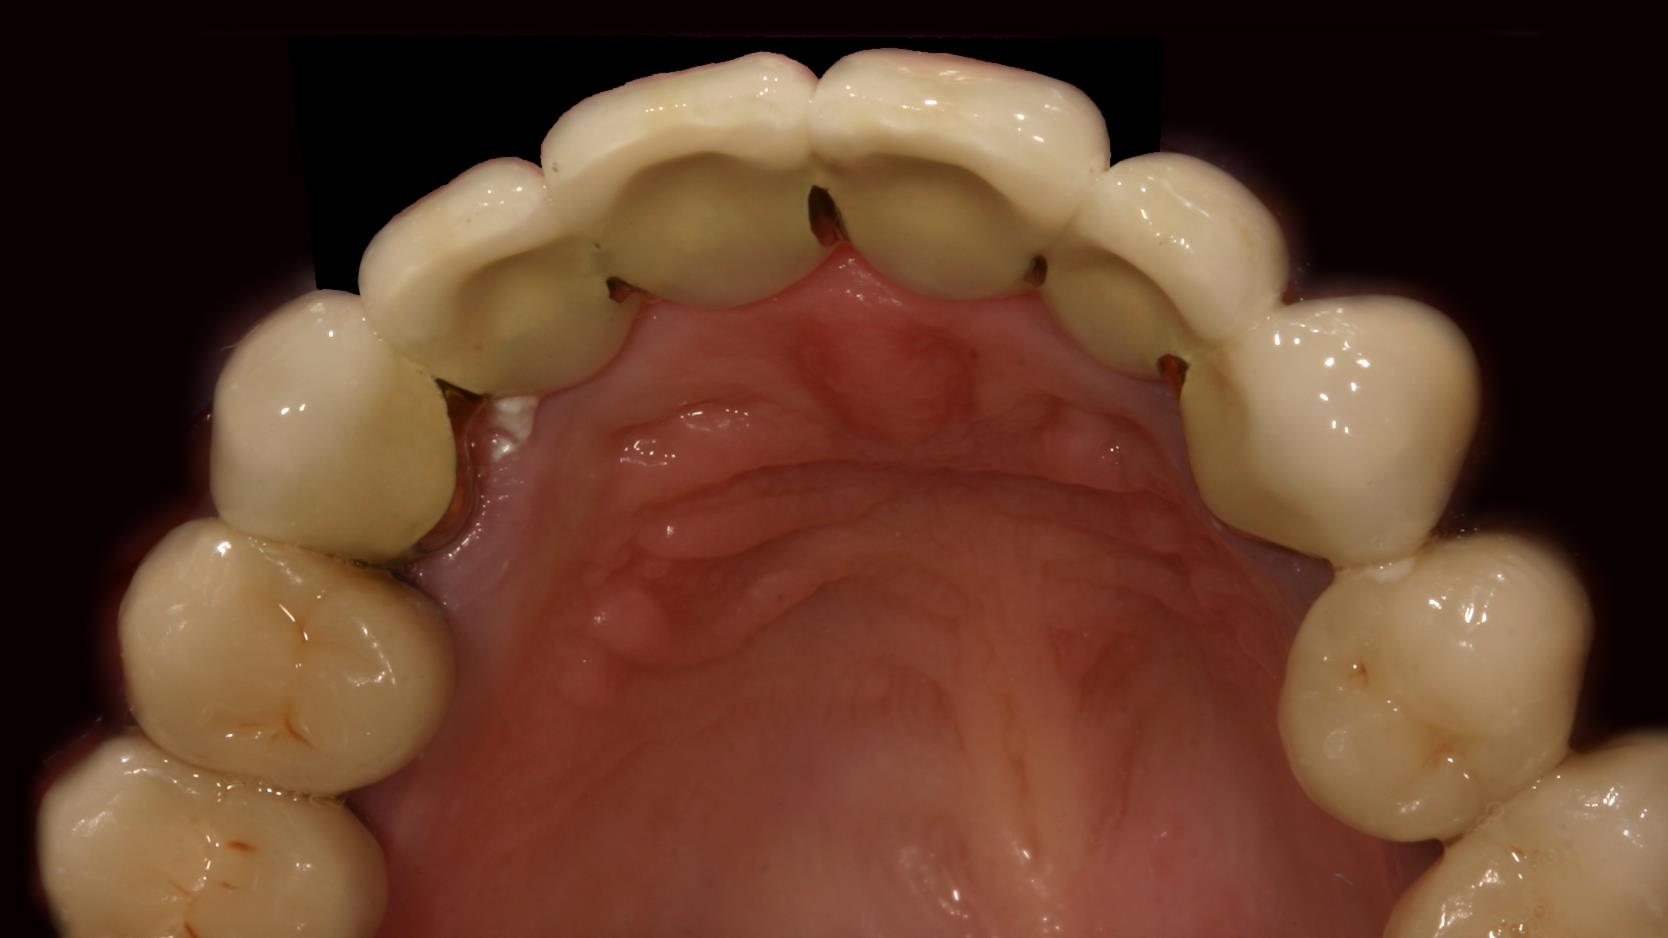

Wenn mehrere Zähne im Frontzahnbereich fehlen, kann man die Lücke durch eine Brücke schließen. Meistens ist dann auch schon der Kieferkamm zurückgeschwunden. Dadurch wirken die Brückenglieder länger. Auch die Zahnfleischpapille fehlt. Hier haben wir sie mit rosa Keramik nachgebildet, um „dunkle Löcher“ zwischen den Zähnen zu vermeiden und die Zähne nicht unnatürlich breit und lang erscheinen zu lassen.